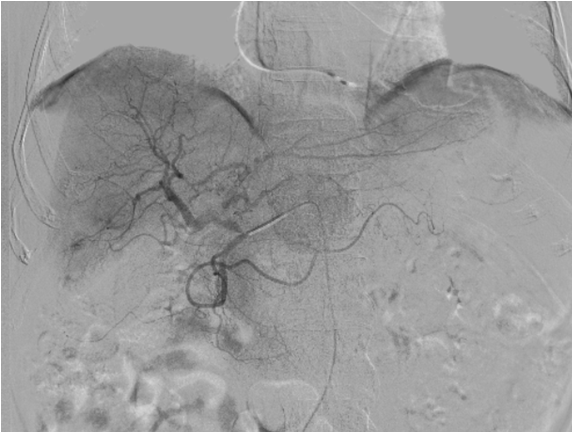

Transarterial Chemoembolisation (TACE) is a minimally invasive, image-guided treatment used primarily for liver cancer, especially hepatocellular carcinoma (HCC). It is commonly recommended when surgery or ablation is not suitable.

Liver tumors receive most of their blood supply from the hepatic artery, whereas healthy liver tissue is supplied mainly by the portal vein. TACE uses this difference to selectively target the tumor.

During the procedure, chemotherapy is delivered directly into the tumor-feeding arteries, followed by embolic agents that reduce blood flow. This traps the chemotherapy within the tumor and deprives it of oxygen and nutrients, limiting tumor growth while reducing systemic side effects.

Transarterial Chemoembolization (TACE) is a minimally invasive, image-guided procedure used to treat liver tumors. Through a tiny catheter placed in an artery, targeted chemotherapy is delivered directly to the tumor, followed by embolization to block its blood supply—maximizing tumor control while minimizing effects on the rest of the body.